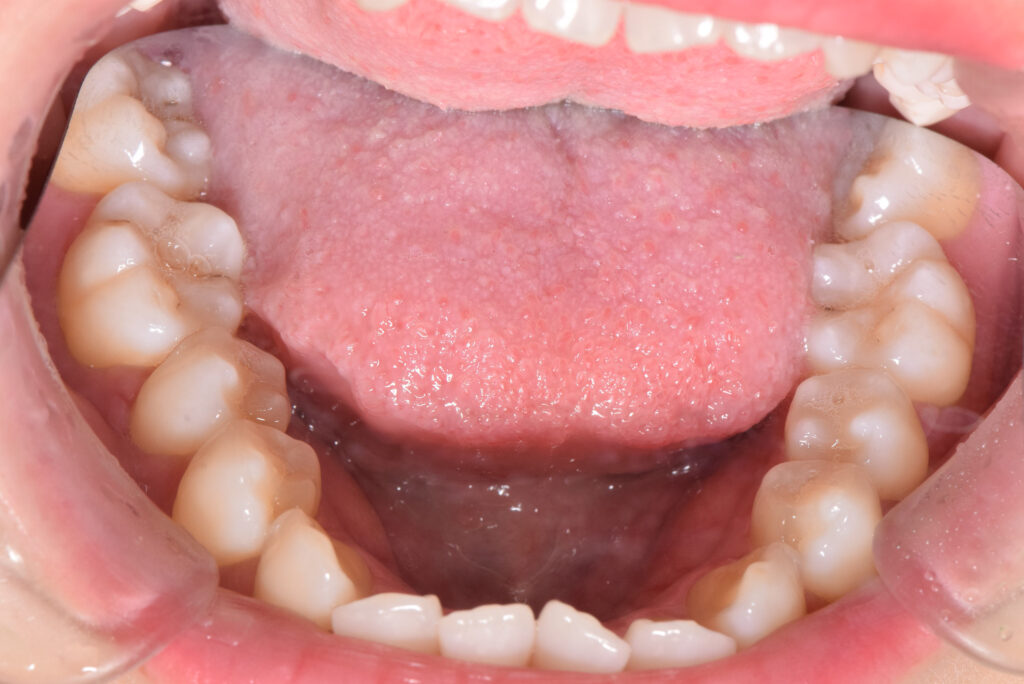

下顎

治療前